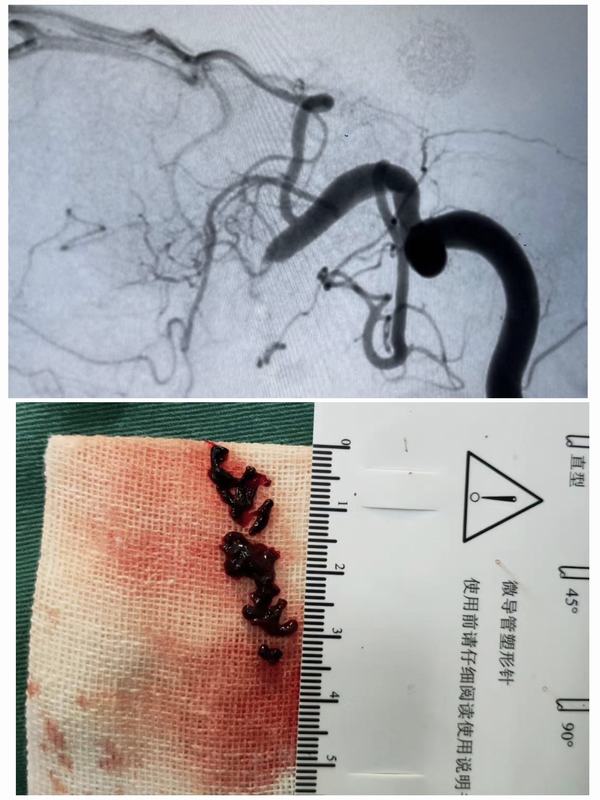

2月23日中午12:00,腦病急診科接診一名59歲女性患者,急性起病,主因:突發(fā)左側(cè)肢體無力1.6小時(shí)。經(jīng)查體患者神志清,精神差,言語不利,左側(cè)肢體肌力0級(jí)。立即開通綠色通道,急查頭顱CT示:右側(cè)基底節(jié)區(qū)及右側(cè)側(cè)腦室前角旁多發(fā)腔梗。家屬簽字同意后給予靜脈溶栓治療。12:20患者進(jìn)入導(dǎo)管室行全腦血管造影+動(dòng)脈溶栓術(shù)+機(jī)械取栓術(shù)。患者于3月3日出院,出院時(shí)患者神志清,精神狀態(tài)良好,左側(cè)肢體肌力正常、言語清晰,入院時(shí)癥狀得到完全緩解。

腦卒中具有高發(fā)病率、高致殘率、高死亡率、高復(fù)發(fā)率的特點(diǎn),給社會(huì)、家庭帶來了沉重的負(fù)擔(dān),但只要4.5-6小時(shí)內(nèi)進(jìn)行靜脈溶栓,必要時(shí)動(dòng)脈取栓的積極治療,多可獲得更好的療效。